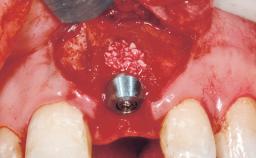

A 30-year-old female patient had lost tooth 21 and was referred to our clinic for consultation and treatment. Due to advanced apical infection, tooth 21 had been extracted two months earlier at another clinic and an acrylic-resin tooth had been bonded to the adjacent teeth. The patient desired implant treatment to avoid any damage to the adjacent natural teeth. While the patient had no history of any systemic disorder, she was a heavy smoker and exhibited medium to advanced periodontitis in the entire jaw. After the initial treatment to achieve a pocket probing depth of less than 4 mm and no bleeding on probing, a decrease in the height of the papillae mesial and distal to the extraction site and overall gingival recession were observed.

Type of Implants One-Piece|Reduced-Diameter

Bone Augmentation Horizontal|Staged

Augmentation Materials Autogenous chips|Membrane

Placement Protocol Early or late implant placement